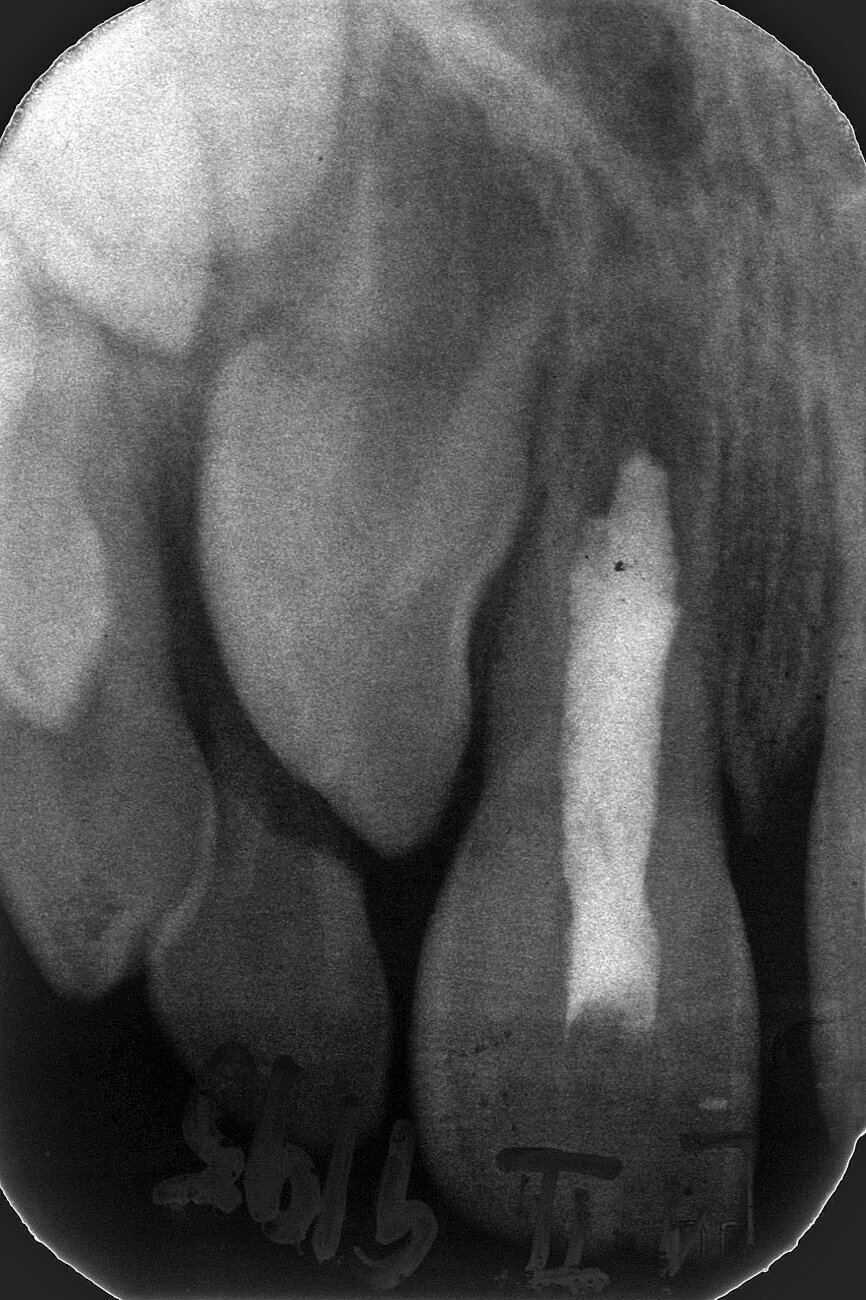

Case 3: Female (born 8 August 1988): Tooth 11

Fig. 5a: 4 September 1995 ante RCF

(non-vital).

Fig. 5b: 4 September 1995 post RCF

Fig. 5c: 22 April 2002 status.